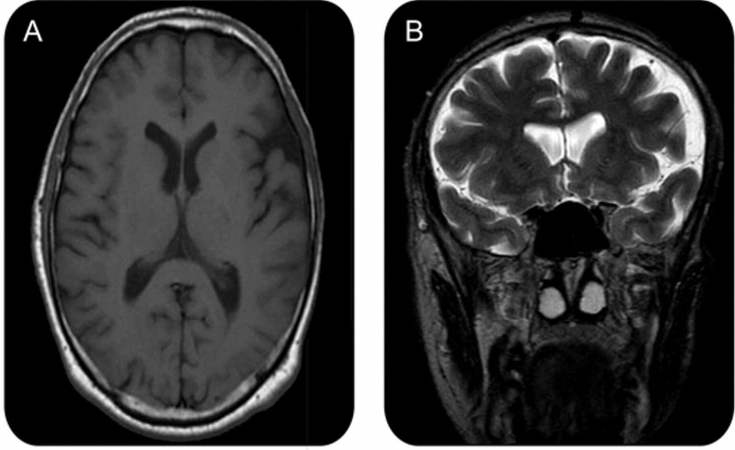

10% of those affected develop a seizure disorder as part of the disease. Epileptic seizures, as a rule, are Jacksonian in nature (characterized by contraction of the muscle group, which subsequently spread to neighboring muscles) and occur on the side opposite the affected side of the face. Half of these cases are associated with abnormalities in both the gray and white matter of the brain — usually ipsilateral, but sometimes contralateral — which are detected during magnetic resonance imaging (MRI) scans.

Diagnosis can be made solely on the basis of the history and physical examination of people who have only facial asymmetry. For those reporting neurological symptoms such as migraine or seizures, brain MRI is the imaging modality of choice. Diagnostic lumbar puncture and serum autoantibody testing may also be indicated. Oligoclonal bands and an elevated IgG index can be detected in 50% of patients.